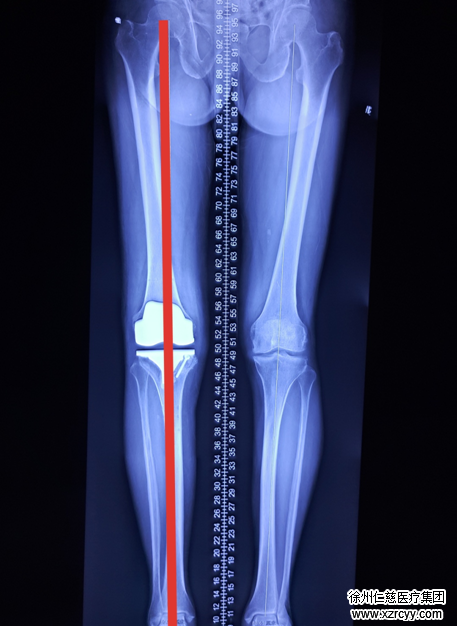

术后片

betway在线登陆去年底与德国贝朗医疗集团合作,成立淮海经济区首个“精准医疗计算机辅助导航关节置换中心”,引进贝朗关节产品,已完成数十例全膝关节手术,所有患者均获得满意力线恢复,膝关节功能得到极大改善。